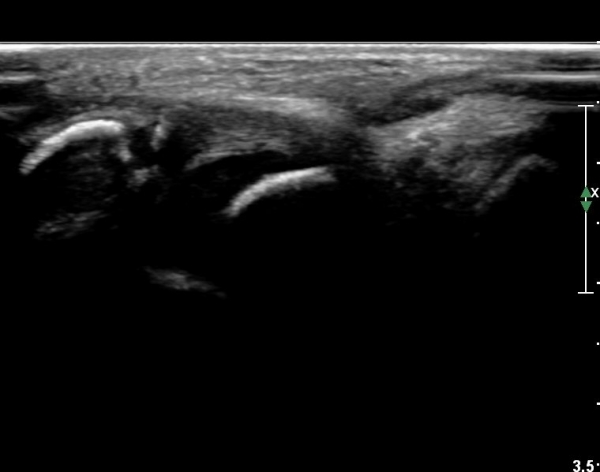

ÃÊÀ½ÆÄ °Ë»ç